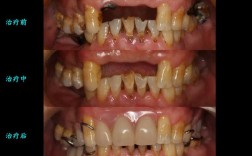

- 关注案例效果:要求查看医生过往的矫正案例,尤其是与自己情况相似的案例,观察矫正后的牙齿排列、面部改善效果,这能直观反映医生的技术水平。